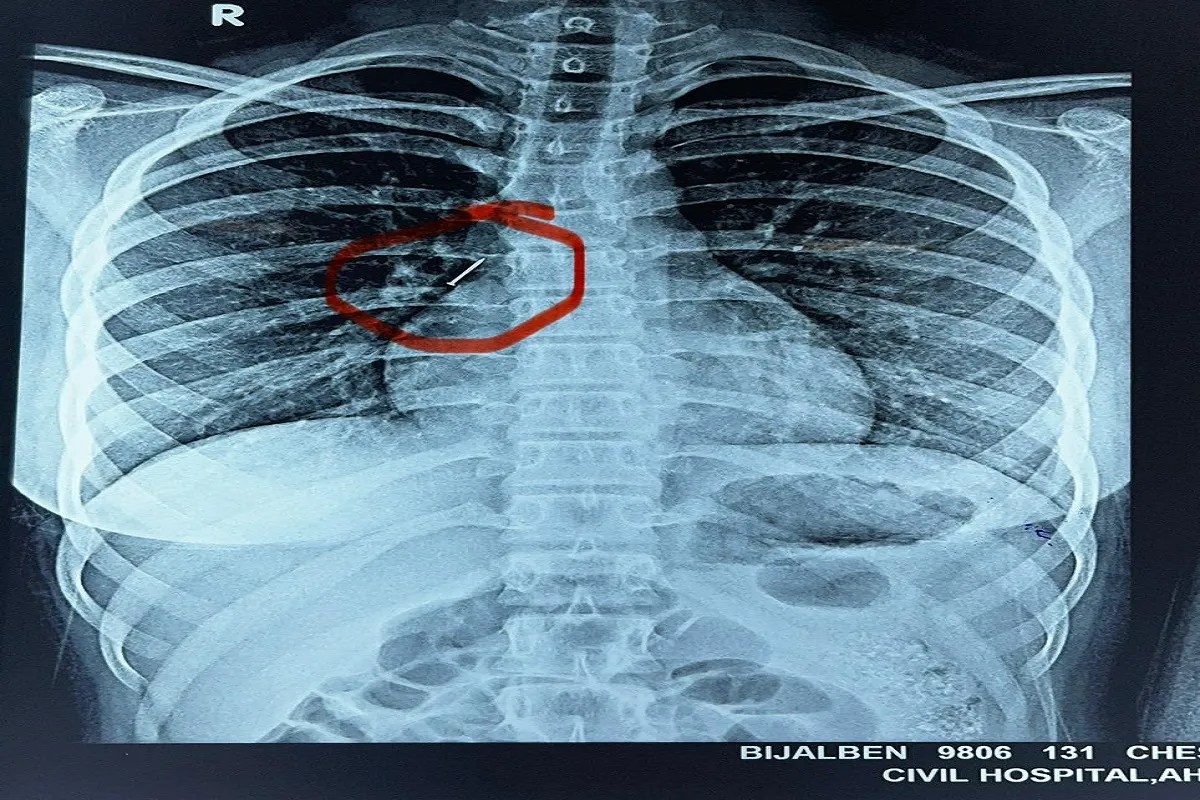

मरीज का एक्स-रे, जिसमें दिखाई दे रही है पिन।

सांस लेने में हुई कठिनाई के चलते परिजनों ने पहले मोडासा और फिर हिम्मतनगर अस्पताल में भर्ती कराया, लेकिन स्थिति गंभीर होने पर उसे अहमदाबाद सिविल अस्पताल रेफर किया गया। जहां ईएनटी विभाग के डॉक्टरों ने मात्र दो मिनट में ब्रॉन्कोस्कोपी के माध्यम से पिन निकालकर बच्ची को नया जीवन दिया।फेफड़ों के बेहद पास पहुंच गई थी पिनसिविल अस्पताल के ईएनटी विभाग के प्रोफेसर डॉ. कल्पेश पटेल और उनकी टीम ने एक्स-रे रिपोर्ट में देखा कि नुकीली पिन फेफड़ों के बेहद पास श्वास नली में फंसी हुई है। एनेस्थीसिया विभाग की डॉ. भावना रावल और पल्मोनोलॉजिस्ट डॉ. नलिन शाह के सहयोग से ब्रॉन्कोस्कोपी की गई। अत्यंत सावधानी से मात्र दो मिनट में पिन बाहर निकाल ली गई। पिन निकलते ही बच्ची की सांसें सामान्य हुईं और परिवार ने राहत की सांस ली।